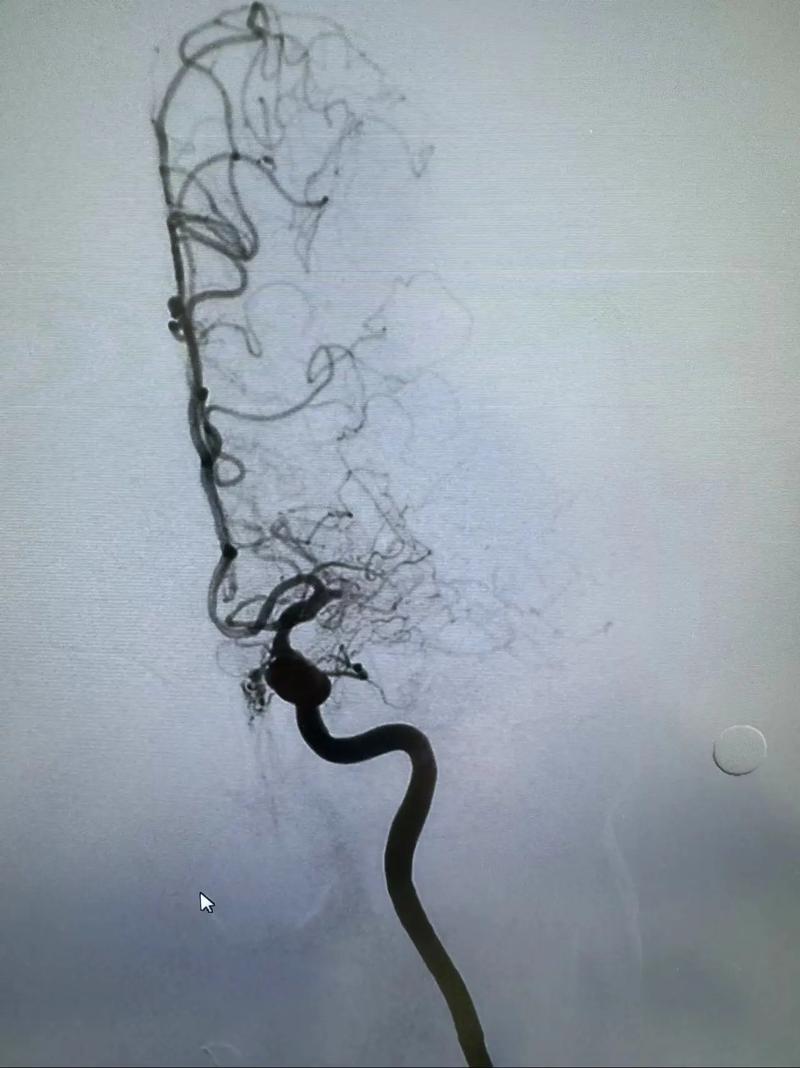

- DSA (数字减影血管造影):这是诊断脑血管病的“金标准”,在评估阶段,如果高度怀疑需要手术,医生可能会建议直接做DSA,一旦明确,即可同期进行支架植入术,避免患者再次住院。

- 植入支架:在X光造影的引导下,将球囊扩张支架送到狭窄处,然后释放球囊撑开支架,使血管恢复通畅。